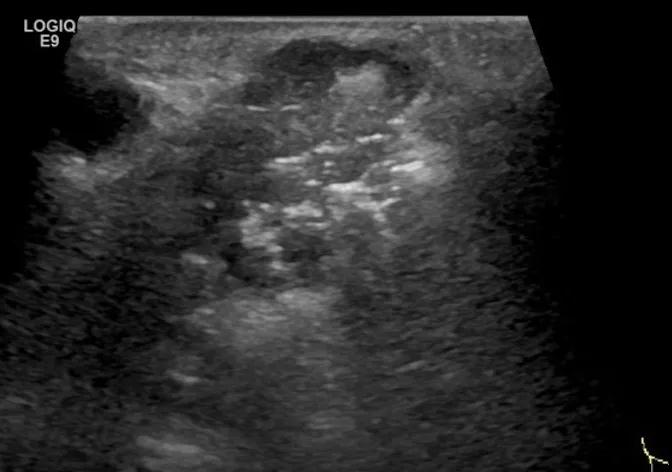

第三例是甲状腺癌患者,双侧甲状腺癌切除术后、碘治疗后一年余效果欠佳,超声显示左颈3区3枚低回声结节,穿刺示甲状腺乳头状癌转移。患者不愿意手术,希望采取局部治疗。对病灶进行液体隔离后采取热消融术,由于淋巴结较小,热消融一分钟左右完全灭活,术后增强影像显示没有脏器充填。

(病例3图例)